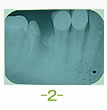

症例3 2008 10/18 更新

2016 3/21更新

治療前

治療前 治療完了

抜歯後

(下11本、上1本抜歯済み)

平成19年6月29日

治療完了

平成21年1月29日

(治療期間:1年7ヶ月)